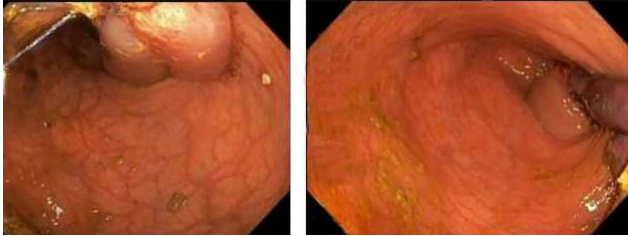

Figure B showing the lipomal stalk base

Figure C showing the large stalk of the lipoma and also internal hemorrhoids.

An 81-year-old man with history of coronary artery disease on Plavix presented with a large mass protruding from his anus. The patient was straining during defecation and felt severe abdominal and rectal pain. Vital signs and labs were normal. Physical examination revealed left lower quadrant tenderness, and a large mass protruding through his anus. Computed tomography (CT) scan of the abdomen and pelvis revealed a prolapsed 7x5cm sigmoid lipoma with coloanal intussusception, without evidence of obstruction, perforation, or peritonitis (figure A). Attempts to reduce the lipoma manually at bedside were unsuccessful, therefore the patient was taken for emergent resection. The gastrointestinal team was asked to assist so that direct visualization could be used to resect the lipoma stalk. A pediatric colonoscope was inserted alongside the lipoma into the rectum revealing a large stalk of prolapsed colon extending to 20cm from the anal verge (figure B). The retroflexion view showed the stalk traversing the anus surrounded by large hemorrhoids (figure C). The colonoscope could not be advanced past the stalk due to intussusception from the lipoma stalk pulling the colon forwards. Endoloops and a LigaSure device were used to transect the lipoma since the patient was on Plavix and had a high bleeding risk. Using the colonoscope for constant visualization, two Endoloops were placed manually to 10cm from the anal verge using caution to avoid anchoring onto the colonic wall. A third Endoloop was placed at the junction of the lipoma and its stalk at the anal verge. The colonoscope was removed and an Impact LigaSure device was used to slowly transect across the apex of the lesion right at the anal verge with manual pressure to retract the skin, perianal region, rectal mucosa, and hemorrhoids from the LigaSure device (figure D). The colonoscope was then reinserted and the colon was easily traversed up to 40 cm from the anal verge. The stalk was noted to have the two Endoloops in place without bleeding. Pathology revealed a submucosal lipoma with acute inflammation and partial fat necrosis as well as overlying colonic mucosa with ulceration (figure E).